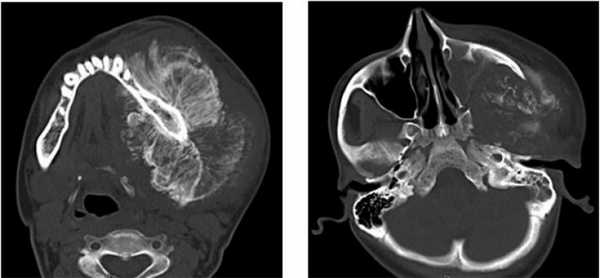

Пациент муж., 16 лет, в анамнезе удаление зуба год назад. Обратился с жалобами на резкое увеличение объема лица слева, дисфагию и трудности при разговоре в связи с давлением опухолевой массы на глотку (Рис. 2,3).

Рис. 2. КТ свидетельствует об остеосаркоме, поражена левая половина верхней челюсти, вовлечены крыловидный отросток и нижняя челюсть с инфильтрацией в виде солнечных лучей и выраженной периостальной реакцией. Ассоциированные деформация и отек мягких тканей.

Рис. 3. 3d-реконструкция остеосаркомы с деформацией и отеком мягких тканей.